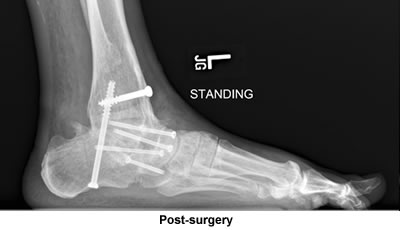

It's been approximately seven and one half months since you performed triple arthrodesis on my left foot and the results of that surgery have given me back a big part of my life that has been missing for many years, now being able to walk, jump and put all sorts of stress on the foot without any pain. I just bought a pair of sandals that gives one about zero support on the ankle; I hadn't been able to wear sandals for over thirty years. I can also now walk barefoot on lumpy sandy beaches here on the Cape and the list goes on!

I was all set to have the surgery done elsewhere on just one joint. Casually looking through the Cape Cod Times and spotting your ad for surgery on all sorts of foot problems and stating you were also available for consultation at your office in Bourne immediately convinced me to visit you as I did have some reservations about the surgery I was about to have. I figured that you would confirm that surgery, but that was not the case; you told me three joints were gone and needed fusions. You sent me a very convincing email and also fit me into your surgery schedule much sooner than normally would be expected because of your full workload. I just can't thank you enough for what your surgery has done for me.